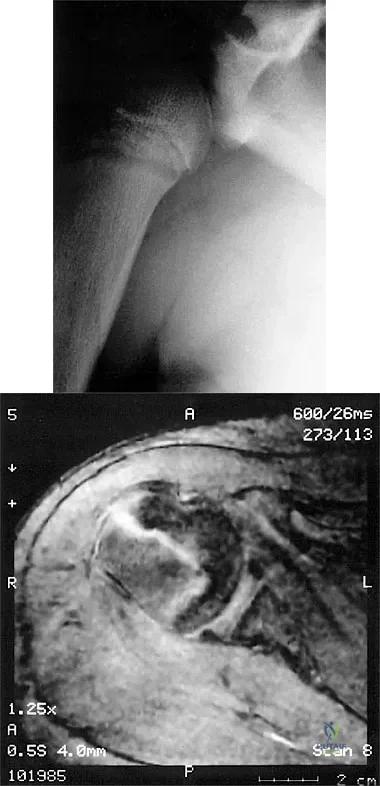

Question 62

Based on the MR arthrogram of the elbow shown in Figure 8, which of the following structures is torn?

Explanation